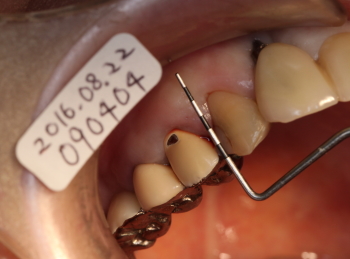

ポケット測定

短針を挿入した像

かなり深い